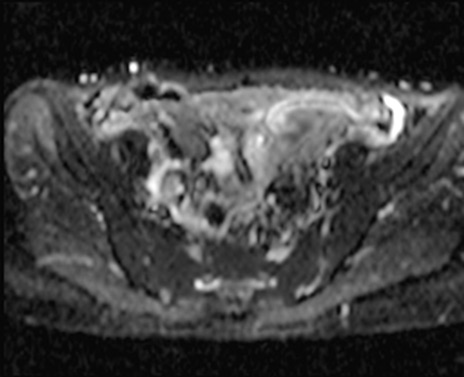

MRI(4日後)